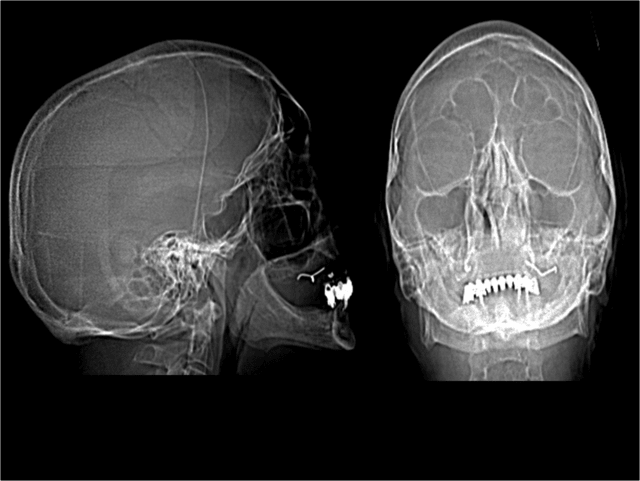

Etude en vue d'une extraction implantation pour la réalisation d'un bridge transvissé sur implants master-L.

Compte tenu de l'ampleur des lésions periapicales, l'implantation immediate est dans ce cas contre indiquée.

Question : c'est quoi au maxillaire ? Des implants ?

> Question : c'est quoi au maxillaire ? Des implants ?

tu as retrouvé un de mes premiers juxta osseux?